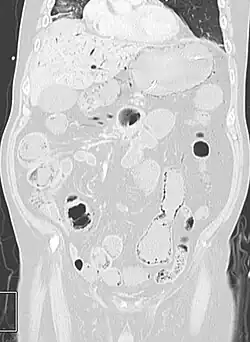

Coronal reformatted MDCT image showing extensive pneumatosis intestinalis in the left upper quadrant small bowel. The pneumatosis is more cystic and nodular in the small bowel in the midline and the right of midline. This patient had a relatively benign presentation without bowel ischemia and was treated conservatively.